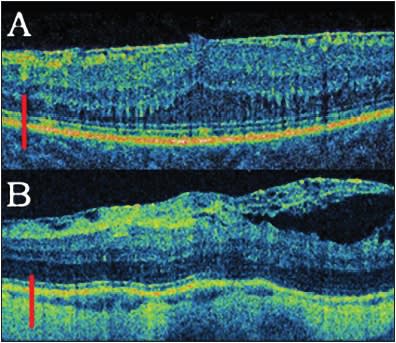

Schumann et al. recently reported that remnants of vitreous on the surface of the ILM may be found after both spontaneous and surgically induced posterior vitreous detachments. These remnants of vitreal collagen may play a role in ERM formation.4 Additionally, they found fibrocellular proliferations on the vitreal side of the ILM (removed during vitrectomy for macular hole), with predominantly fibrous astrocytes in samples after first vitrectomy and predominantly myofibroblasts and fibroblasts in samples after second vitrectomy.5 This theory may be partially confirmed by our spectral-domain OCT findings, which showed that, during follow-up, condensation of posterior hyaloid or vitreous traction preceded ERM formation (Figure 1).5 This suggestion was also confirmed by different authors in both older and more recent publications.4,5,6

Figure 1. Situations preceding ERM formation. A. Vitreomacular traction on spectral-domain OCT. B. Condensation of the posterior hyaloid.